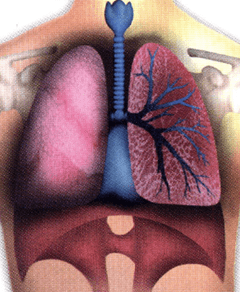

أنفُث، إِلهث، إلى الداخل، إلى الخارج، خذ شهيقاً، أخرج زفيراً… تقوم منظومة التنفس الخاصة بالجسم، أو الجهاز التنفسي، بالحصول على العنصر الحيوي بالنسبة له، وهو الأكسجين، من الهواء المحيط ونحن نحتاج إلى الأكسجين الذي يلعب دوراً في كيمياء الجسم، إذ يقوم بتجزئة سكر الدم (الجلوكوز)، وإطلاق الطاقة الموجودة به، والتي تزود بالقوة جميع العمليات الحيوية والأنشطة التي يؤديها الجسم تقريباً. والأجزاء الرئيسية للجهاز التنفسي هي: الرئتان، واللتان يتم الوصل إليهما عبر سلسلة متتالية من المسالك الهوائية التي تؤدي بنا إلى الأسفل عبر الأنف، والحلق، والقصبة الهوائية.

حجم و شكل الرئتين

• تكون كل رئة تقريبًا على شكل مخروط.

• تصل النقطة العليا للرئة أو «الرأس» موضعاً أعلى قليلاً من عظمة الترقوة، مروراً بقمة الصدر في اتجاه الكتف.

• تستقر القاعدة العريضة للرئة فوق عضلة التنفس الرئيسية قوية الشكل، والتي تُعرف باسم الحجاب الحاجز، والتي توجد تقريباً في ذات مستوى عظمة الصدر، ولكنها تتقوس إلى أسفل في إتجاه الضلوع السُفلية المحيطة بالجانبين.

• تتميز الرئة اليسرى بوجود جزئين أو فصين رئيسيين، وجزء منها يكون مجوف الشكل حتى يتلاءم مع وجود القلب بداخله.

• تتميز الرئة اليمنى بوجود فصوص ثلاثة، وفي المتوسط يزيد حجمها بمقدار الخمس عن الرئة اليسرى.